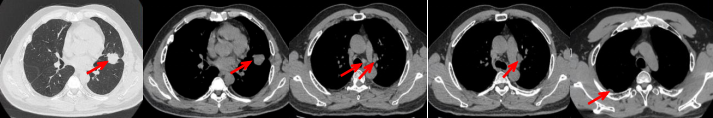

55岁男性,无吸烟史,有饮酒嗜好。2024年11月常规体检胸CT:左肺上叶占位性病变,大小约2.7×2.4cm,恶性可能大;左肺、左侧叶间胸膜及胸膜下多发微小结节,转移待除外。左侧胸腔积液,部分骨质改变。2024年12月初肺穿刺活检,病理:(肺)腺癌。NGS基因检测:CCDC6-RET(exon1-exon12)融合突变阳性(丰度:13.21%)。PD-L1表达阳性(TPS=35%,CPS=45)。

治疗经过:2025.01开始口服普拉替尼(400mg,qd)。2025.03复查胸CT:左肺上叶、右肺上叶、左肺斜裂见多发实性结节影,长径范围约3-17mm,较大者大小约17mm×12mm,位于左肺上叶下舌段,可见分叶、毛刺、胸膜凹陷、棘状突起征象。纵隔内小淋巴结。评效PR,随访中。治疗期间未出现毒性反应。

2024.12

2025.03评效PR